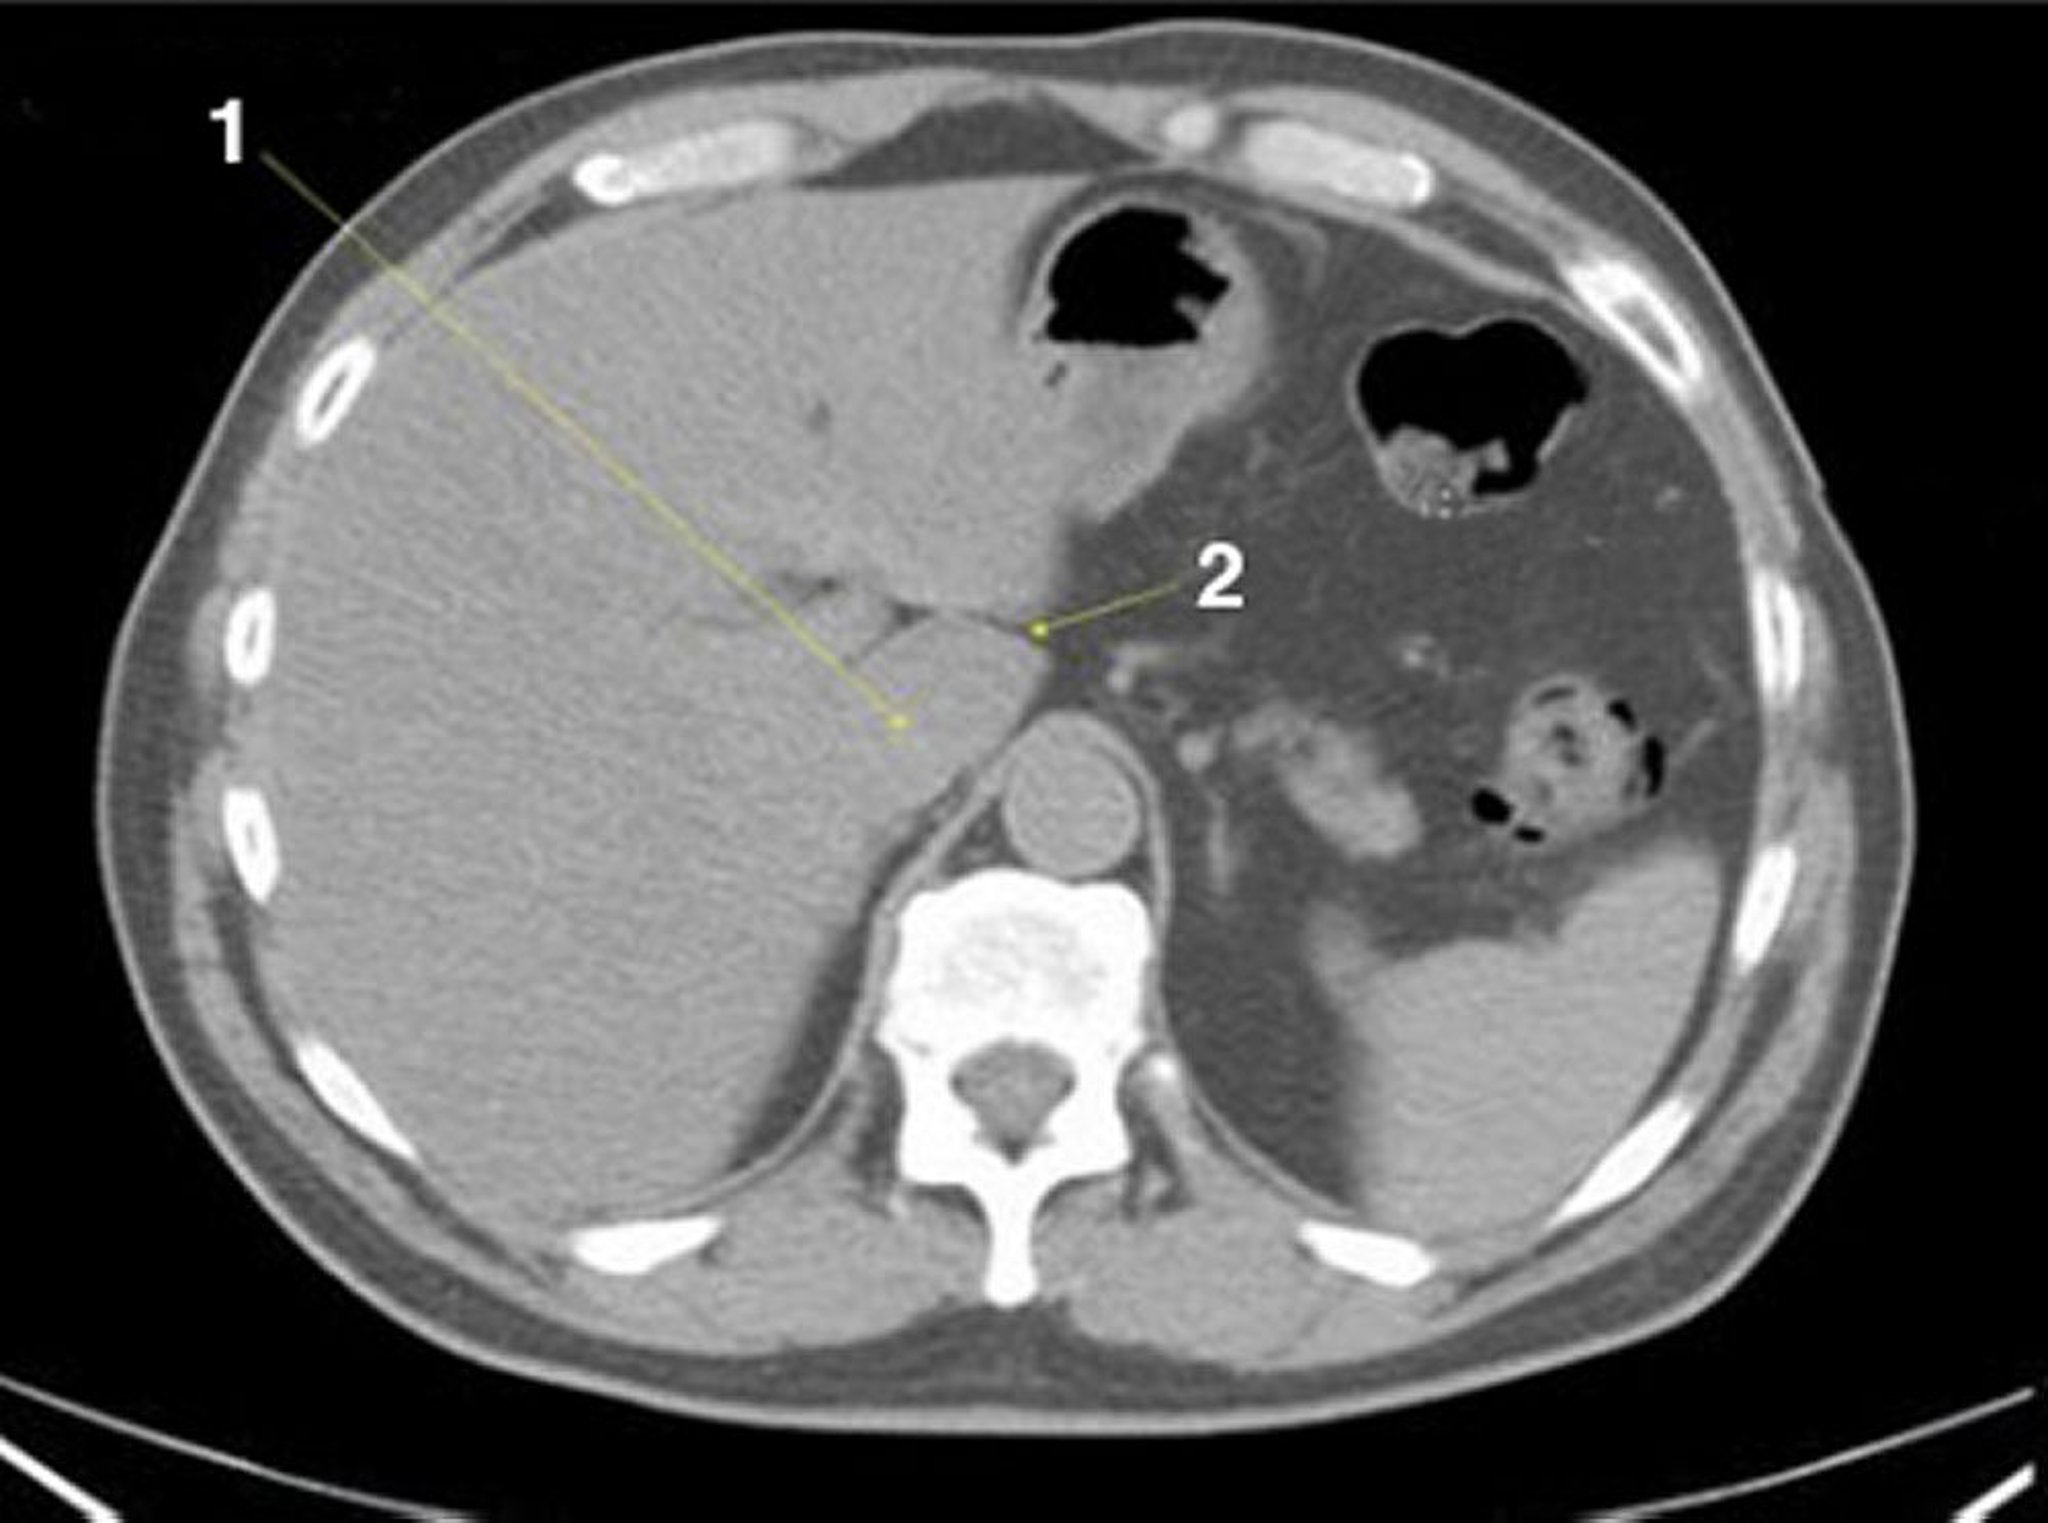

CT-Scan von Abdomen und Becken mit normaler Anatomie ohne Kontrastmittel (Folie 4)

1 = Lobus caudatus der Leber; 2 = Fissur für Ligamentum venosum.